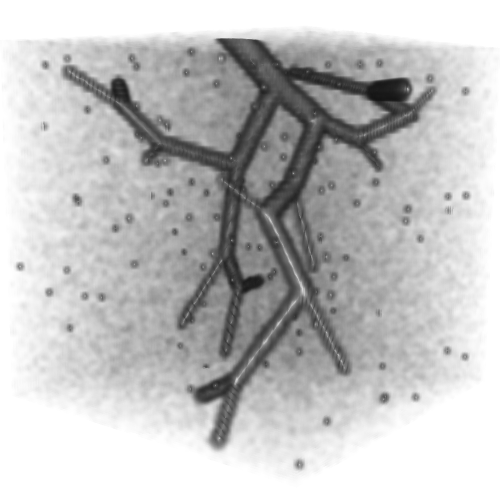

3.1 Connectedness of the Vesselness Map

Fig. 3 shows the connectedness of vessels recovered from state-of-the-art vascular enhancers and curvilinear ridge detectors FFR and OOF together with the proposed CVM for the synthetic HCP and the real PC images.

On the synthetic phantom, FFR shows a fragmented and rough vesselness response in correspondence of irregularly shaped sections of the structure. Also, the response at the bifurcation is not smoothly connected with the branches (triangular loop). Conversely, OOF recovers the phantom connectedness at the branch-point, and the vesselness response is consistent along the tortuous curvilinear section, however ghosting artifacts are observed as the shape of the phantom becomes irregular (C-like) or differs from a cylindrical tube. Also, close convoluted structures, which change scale rapidly in the HCP, produce inconsistent responses of OOF (fig. 3). CVM shows here a strongly connected vesselness response in correspondence of both regular and irregular tubular sections, with local maxima at structures’ mid-line. The connectedness of the structures is emphasized regardless the complexity of the shape, and it resolves spatially the tortuous curvilinear ‘kissing vessels’ without additional ghosting artifacts, despite the smooth profile.

Similar results are observed on the PC dataset: FFR has a poor connected response in the noisy and low-resolution image. Vessels are overall enhanced, however thin and fragmented structures remain disconnected. Overall, the vesselness response is not uniform within the noisy structures, where maximal values are often off-centred. A more consistent response is obtained from OOF, where the connectedness of vessels is improved. Maximal response is observed at the mid-line of vessels, however, noise rejection is poor. CVM strongly enhances here the vessel connectivity. The fragmented vessels of PC have a continuous and smooth response in CVM with higher values and a more defined profile. Large vessels shows solid connected regions with local maxima at mid-line as in OOF. Conversely from OOF, CVM shows improved noise rejection in the background.

The respective tensor fields (TF) synthesized on both HCP and PC show consistent features. The TF’s characteristics are in line with the connectedness of CVM: enhanced and connected vessels are associated with high anisotropy, whereas background areas show a predominant isotropic component.